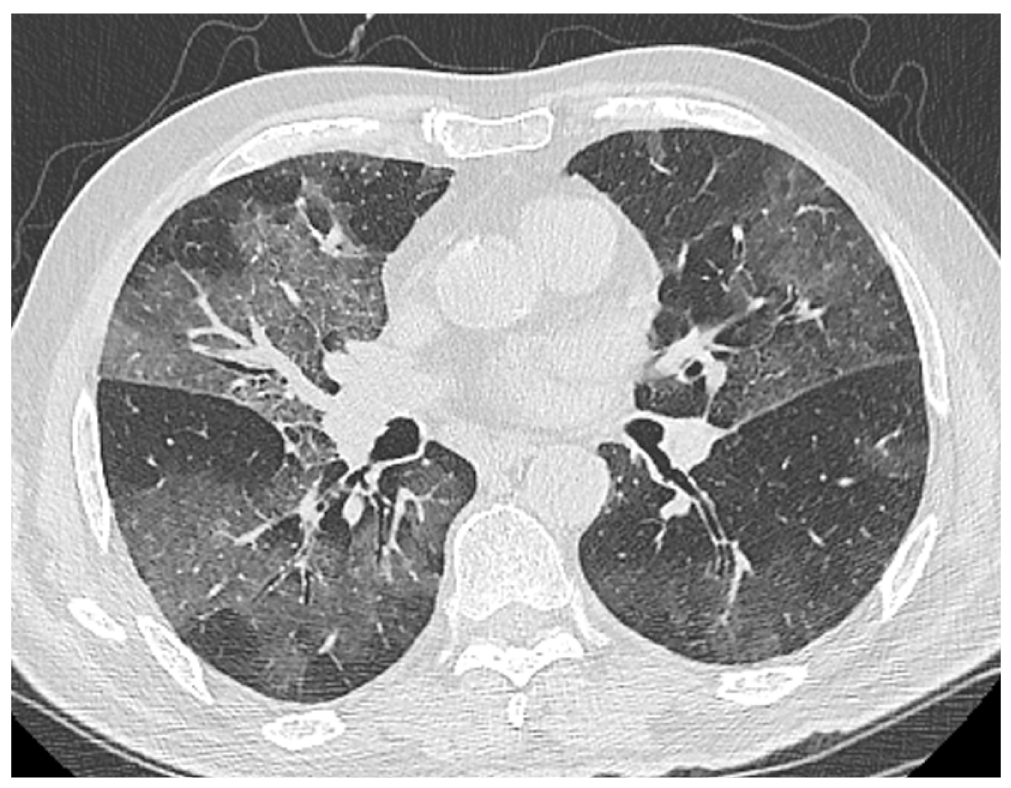

Степень специфических изменений в легких, по радиологическим данным, оценивалась как КТ-2 (см. табл. 1; рис. 5). Течение инфекции было отягощено сопутствующей болезнью Паркинсона, гипертонической болезнью, фибрилляцией предсердий, перенесенным ишемическим инсультом от 2020 года, протяженным стенозом позвоночного канала на уровне L1–L5. За время пребывания в инфекционном отделении пациент получал терапию ГКС, тоцилизумабом, антибактериальную терапию меропенемом, линезолидом. Проводилось переливание плазмы крови с антителами к COVID-19.

Рис. 5. Пациент Л., 75 лет: компьютерная томограмма органов грудной клетки свидетельствует о пневмонии средней степени тяжести (КТ-2). / Fig. 5. Patient L., 75 years old: computed tomography of the chest organs indicates moderate pneumonia (CT-2).